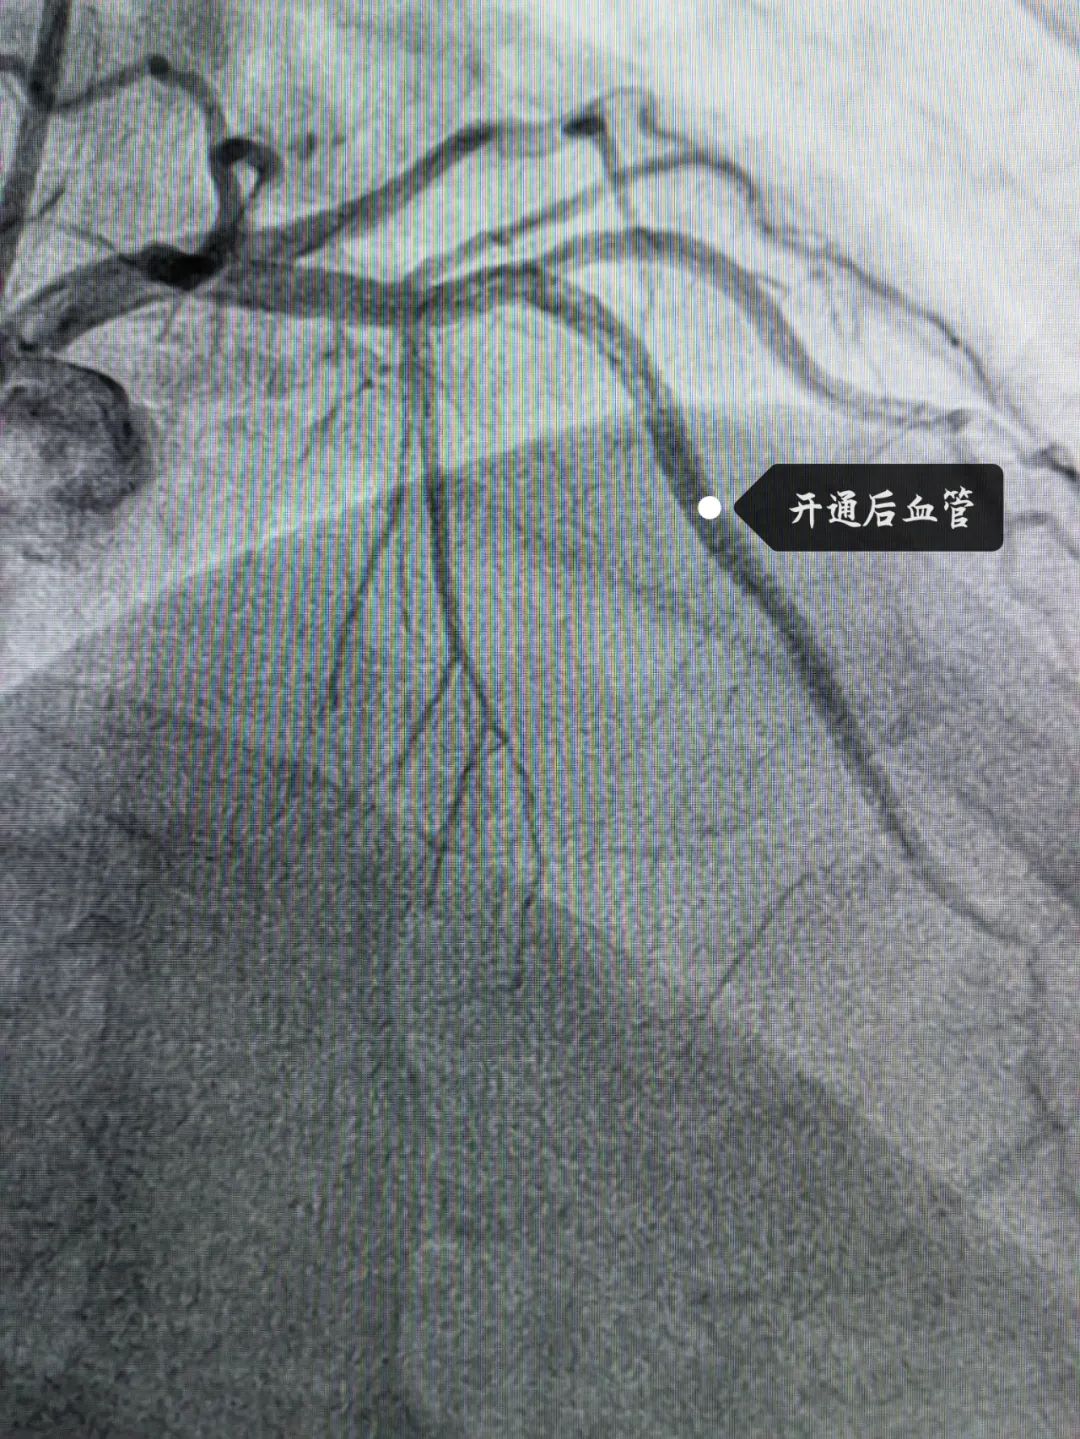

这位患者是位90后,因突发胸闷持续20余小时才来医院治疗,考虑到小伙子胸痛反复,无法缓解,病情危急,九龙湖院区心内科团队立即查找原因,原来小伙子最重要的一支心脏血管:“前降支”急性闭塞且血栓负荷重。于是,球囊扩张、血管内溶栓、支架植入......紧张又有序地手术操作结束后,小伙子闭塞的血管终于打通,胸痛症状也得到了明显缓解。

可是,张叔叔明明年纪不大,为什么一个呼吸道感染就会导致心衰这么危险的疾病呢?原来,张叔叔的心脏血管“前降支”出现了慢性闭塞。于是,心内科手术团队在血管内超声指导下精准植入2枚支架,使张叔叔的前降支血流恢复畅通。手术后,张叔叔的胸闷症状明显缓解,运动耐力也明显恢复,射血分数也由术前的42%显著回升到50%。